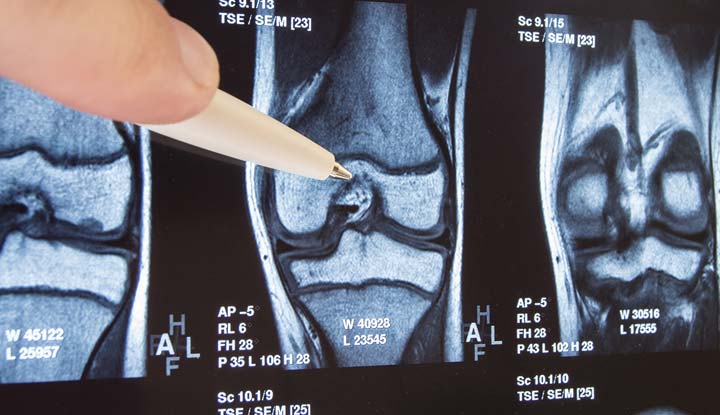

X-rays are commonly used to diagnose osteoarthritis, as they can reveal changes in joint structure. The problem is that by the time osteoarthritis is visible on an X-ray, the joint is already damaged. Research suggests, however, that earlier diagnosis may be possible.

Blood Biomarkers May Reveal Osteoarthritis Eight Years Before X-Rays Can

Researchers from Duke University conducted a study to find blood markers that could predict the development of knee osteoarthritis in women before any joint damage is visible on X-rays. In a group of 200 women, they found that just six specific blood proteins were able to indicate a 77% risk of developing OA, up to eight years before it could be seen on X-rays.

Predicting OA based on these blood markers was more accurate than using age, body mass index (BMI) or reports of knee pain, all of which showed much lower accuracy (51% for age and BMI, 57% for knee pain). The findings suggest that the joint tissue may already be undergoing changes long before OA is visible on an X-ray, hinting at an ongoing inflammatory process or “OA continuum.”

“This tells us that there is an osteoarthritis continuum,” lead study author Dr. Virginia Byers Kraus told The New York Times. “You’re already on an escalator that’s leading you up the path to symptoms and X-ray changes way before we thought.” One day, a blood test may be used to diagnose osteoarthritis in its early stages, when treatment may be able to stop joint damage from occurring.